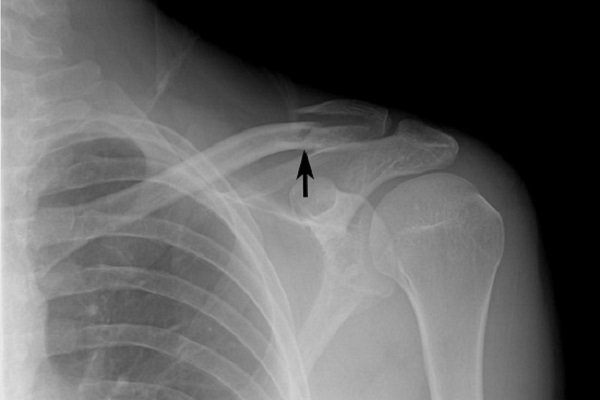

Trật khớp (cùng đòn) xảy ra khi đầu ngoài xương đòn bị bật ra khỏi vị trí tiếp khớp bình thường với mỏm cùng vai, thường do cơ chế ngã đập vai xuống nền cứng hoặc chống tay.

Khi chấn thương té ngã, các khớp cùng – đòn, ổ chảo – cánh tay cũng rất dễ bị giãn hoặc trật ra do hệ thống dây chằng bao khớp không còn vững chắc. Nếu điều trị không đúng và không đủ thời gian, khả năng trật đi trật lại rất cao, làm yếu khớp vai.

Khi bị trật khớp vùng vai, người bệnh cảm thấy đau dữ dội, sưng/bầm tím vùng vai, có thể lan xuống cánh tay. Đồng thời, khớp vai không di chuyển được như bình thường. Nếu trật khớp nặng, xung quanh vùng khớp tổn thương sẽ bị biến dạng, có thể nhìn thấy bằng mắt thường.

1. Gãy, nứt xương

Tình trạng gãy hay nứt xương đòn, xương cánh tay,… xảy ra khi té ngã đập vai hay chống tay. Lúc này, người bệnh sẽ cảm thấy đau nhức dữ dội, đồng thời có dấu hiệu bầm tím xung quanh vùng chấn thương. Nếu xương đòn bị gãy, vai có thể chảy xệ và không thể nhấc cánh tay lên.